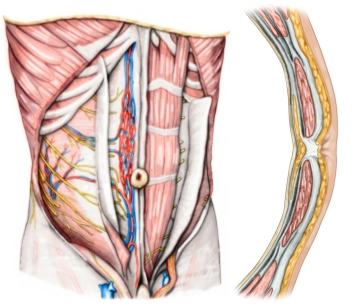

Musculatura Abdominal Anterior e Bainha do Reto

Os músculos abdominais anteriores incluem três músculos muito planos e o M. rectus abdominis:

• Os músculos planos irradiam ventralmente medialmente para a bainha do reto e se inserem nela por meio de um tendão plano (aponeurose). De fora para dentro, encontram-se os seguintes músculos:

• M. obliquus externus abdominis: Dorsalmente, origina-se da fáscia toracolombar, bem como das 7 costelas inferiores e se estende como a lâmina anterior da bainha do reto até a Linea alba mediana, bem como até a crista ilíaca da pelve. Suas fibras correm obliquamente de cranial lateral para caudal medial.

• M. obliquus internus abdominis: Estende-se da Linea alba até a crista ilíaca, bem como até a borda anterior do osso púbico. Suas fibras também correm obliquamente de cranial medial para caudal lateral (em continuação do M. obliquus externus abdominis do lado oposto). Ambos os músculos formam assim uma cruz oblíqua na parede abdominal anterior. Acima da Linea arcuata, irradia para a lâmina anterior e posterior da bainha do reto, abaixo da Linea arcuata para a lâmina anterior.

• M. transversus abdominis: Suas fibras correm da fáscia toracolombar ou das cartilagens costais inferiores e da pelve até a Linea alba ventralmente. Forma principalmente a lâmina posterior da bainha do reto na parede abdominal anterior superior. Abaixo da Linea arcuata, forma a lâmina anterior juntamente com os músculos abdominais oblíquos. A parede posterior dos 3 músculos é formada pela fáscia transversalis.

• O M. rectus abdominis origina-se bilateralmente da cartilagem da 5ª à 7ª costela e se insere no osso púbico perto da sínfise púbica. Por meio de tendões intermediários (intersectiones tendineae), o músculo longo é dividido em vários ventres ("six-pack abs"). Inconsistentemente, o pequeno M. pyramidalis é encontrado caudalmente à frente do M. rectus abdominis, que tensiona a Linea alba. A bainha do reto é assim um canal tendinoso dos músculos abdominais planos, que, além do M. rectus abdominis e M. pyramidalis, contém vários vasos e nervos (Aa. and Vv. epigastricae superior and inferior, Nervi intercostales 5-12).

Para flexão e rotação do tronco, bem como para a prensa abdominal, a parede abdominal anterior é tensionada da maneira descrita pelos dois músculos abdominais oblíquos (M. obliquus externus and internus abdominis, cruz oblíqua), bem como pelo M. rectus abdominis e M. transversus abdominis (cruz reta).